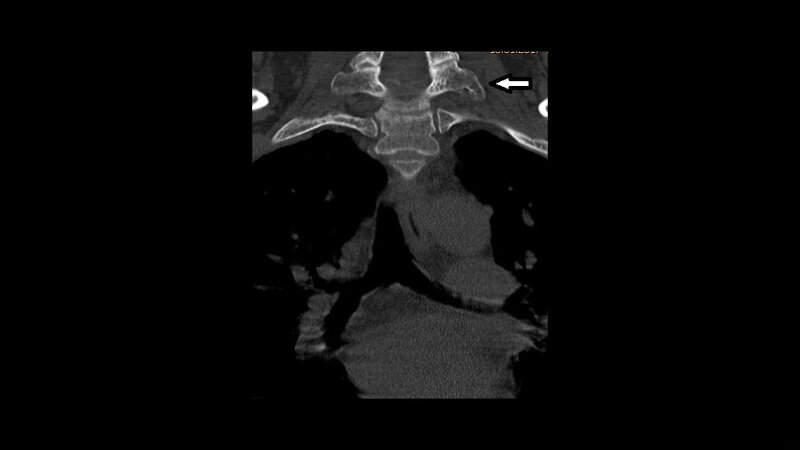

Die Inzidenz der zahlenmäßig varianten Rippenanlagen beträgt 6,3 %. Bei isoliertem Vorkommen handelt es sich um Normvarianten. Zervikale Rippen kommen bei etwa 2 % der Population vor. Sie sind in der Differenzialdiagnose bei supraklavikulären Raumforderungen zu berücksichtigen.

The incidence of abnormal number of ribs in the normal popula-tion is 6.3 %. When isolated, this finding is a normal variant. The prevalence of cervical ribs is 2 % of patients. Differential diagnosis of a supraclavicular mass includes cervical ribs.